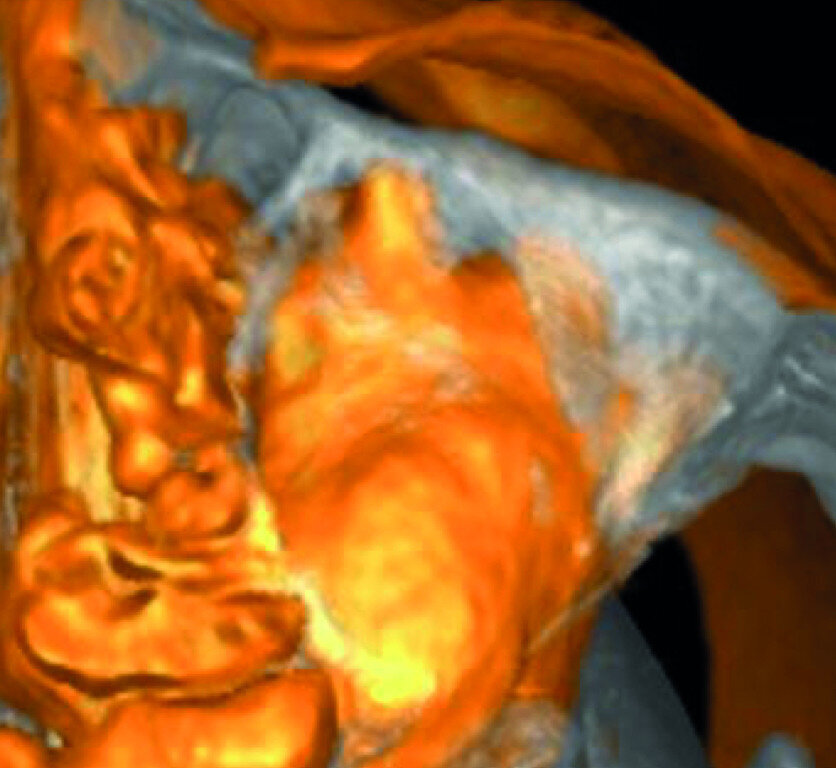

A patient was referred to the office with problems related to separated files. He was a pilot and was complaining of pus draining from his nose when flying. From the preoperative radiograph (Fig. 1), it was clear that there were two separated file fragments in the mesial canals and one cone passing beyond the apex in the palatal root. I requested an iCAT scan, and from this, the left sinus was clearly almost full with inflammatory fluid (Fig. 2) and the cone in the palatal canal was clearly emerging into the sinus. We could also see the two separated files in the two mesial canals clearly in the MPR view (Figs. 3 & 4), as well as another file entering the sinus and not attached to the canal (Fig. 5). We could see the file using different filters (Figs. 6–9), as well as the inflammation inside the sinus and the separated file. We additionally gained a better idea of the location of the cone protruding from the palatal canal into the sinus.

The treatment plan was to try to solve it with a conventional approach and if necessary to perform microsurgery to save the tooth. With the help of H-files, I managed to retrieve the cone from the palatal root, but the files inside the mesial root were impossible to bypass or even to reach with ultrasonic tips. I decided not to overdo it in order to avoid creating an additional problem, like perforating the canal, and decided to seal the canals (Fig. 10). A surgical approach was immediately taken for the mesial canals, cutting 3 mm of the mesial root using the Impact Air handpiece (SybronEndo), and this gave me a direct view of the Schneiderian membrane, where the third file was barely hanging (Figs. 11 & 12). I managed to delicate grab it and to remove it (Fig. 13). Figure 14 shows the postoperative situation, after performing retrograde preparation of the mesial canals.